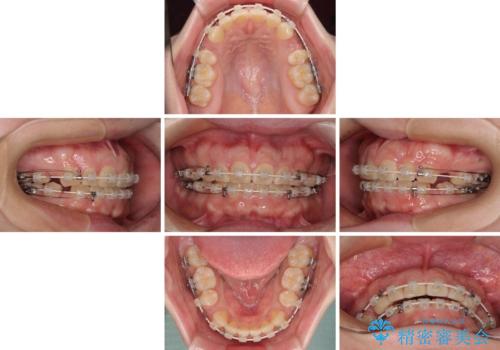

- 矯正装置

- 審美装置

- 2年6ヶ月

- 10-30回